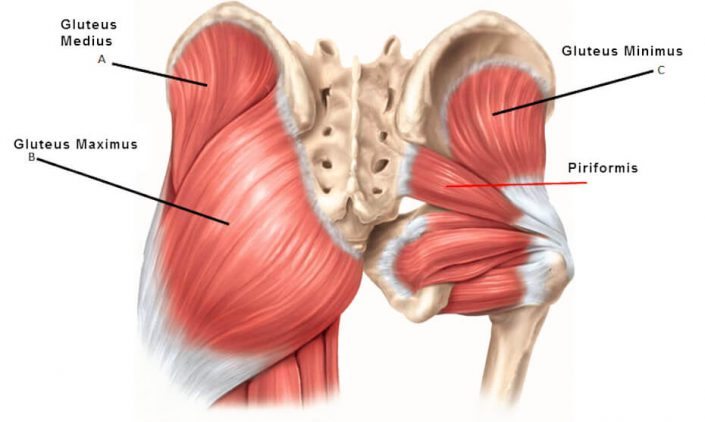

Анатомия мышц: Пириформис

:max_bytes(150000):strip_icc()/human-muscles-illustration-605384917-57ac6b9c3df78cf4597a56f4.jpg)